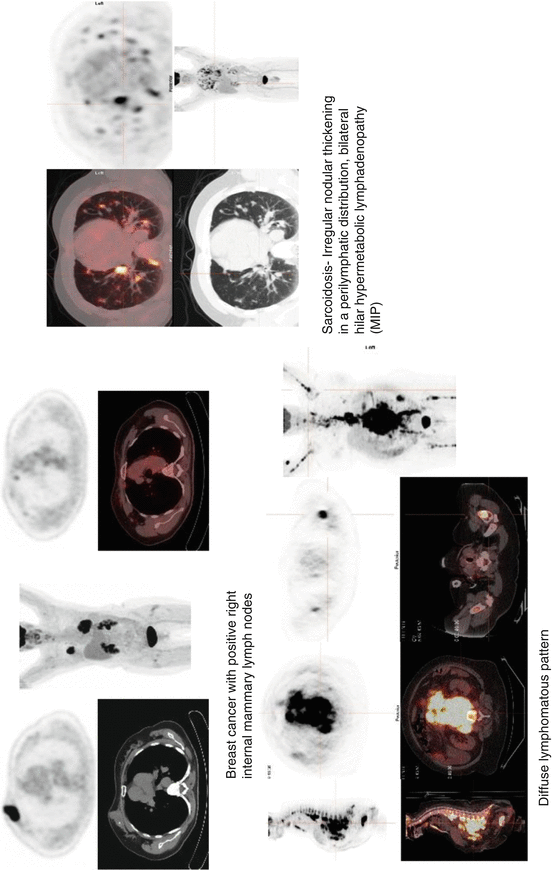

From www.researchgate.net

Overview of selected PET tracers used for monitoring of cancer therapy Fda Approved Pet Tracers Tauvid™, a radioactive diagnostic agent, has been approved by the fda for positron emission tomography (pet) imaging of the brain. Food and drug administration (fda) in 2020 for positron emission tomography. Tauvid has been approved by the u.s. Food and drug administration (fda) in 2020 for positron emission tomography (pet) imaging of adult patients with cognitive impairments. Food and drug. Fda Approved Pet Tracers.